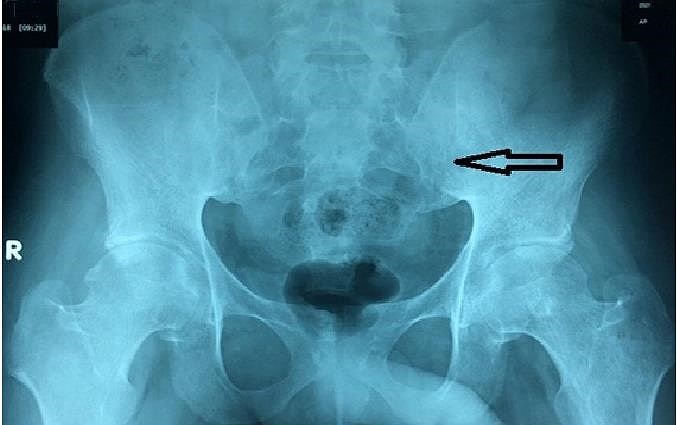

Kết quả chụp X-quang cho thấy khung chậu bệnh nhân bị tổn thương khi nhập viện. Ảnh: BV CUNG CẤP

Trước đó, BV tiếp một bệnh nhân nam 20 tuổi trong tình trạng bất động ở tư thế nằm sấp, ăn uống và vệ sinh tại chỗ kèm đau lưng, đau khớp háng hai bên.

Bệnh nhân cho biết rơi vào tình trạng đau lưng, đau lan xuống hai mông, đi lại hạn chế cách đây năm năm. Bệnh nhân đã điều trị tại một BV địa phương với chẩn đoán đau thần kinh tọa/thoát vị đĩa đệm cột sống thắt lưng.

Hai năm sau, bệnh nhân khám tại một BV khác với chẩn đoán viêm cột sống dính khớp nhưng không cải thiện nhiều sau điều trị nên ngưng. Bệnh nhân tìm đến thầy lang địa phương và được điều trị bằng phương pháp kéo giãn tứ chi và nằm bất động suốt sáu tháng. Tuy nhiên, do tình hình không cải thiện, bệnh nhân tìm đến BV Nhân dân 115.

Chẩn đoán bệnh nhân bị viêm cột sống dính khớp, BS quyết định điều trị bằng thuốc đặc hiệu. Sau sáu tuần điều trị, bệnh nhân có thể đi lại dễ dàng.